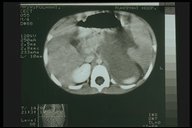

Pancreatic abscess. CT scan showed swelling of the body of pancreas with radiolucent area indicating abscess formation